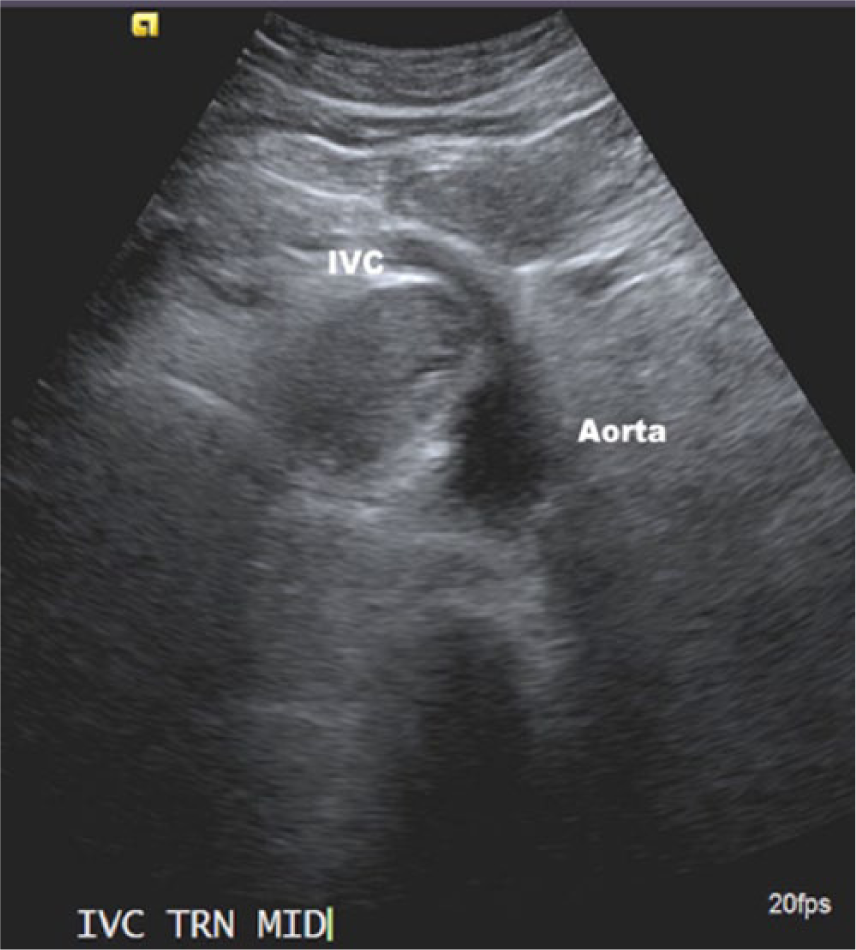

An elderly man in his early seventies was referred to the hospital as an outpatient to undergo an abdominal aortic aneurysm (AAA) screening. The patient had a history of smoking for 20 years. The sonographic examination was performed on an Acuson 2000 ultrasound system (Siemens, Washington, DC), with a curved array C5-2 probe (2-5 MHZ bandwidth). Sonographic findings showed no evidence of an AAA. Velocities and Doppler waveforms throughout the abdominal aorta were normal and showed no significant stenosis. During the examination, the sonographer observed echogenic material in the area of the inferior vena cava (IVC). Upon further examination, the IVC appeared to be thrombosed (Figures 1 and 2). Color Doppler imaging was used to confirm that the IVC was partially obstructed (Figure 3). A transverse view of the IVC and aorta also showed a thrombus in the left renal vein (Figure 4). This prompted the sonographer to extend the examination to the left kidney where a partially exophytic mass located on the anterior/superior portion of the left kidney was seen (Figures 5 and 6). The mass measured 5.43 cm long, 5.31 cm wide, and 4.30 cm anterior-posterior (AP) dimension. Color Doppler imaging showed significant vascularity within the mass (Figure 6). The findings were suspicious for renal cell carcinoma, and the patient shortly thereafter had additional testing with a computed tomography (CT) scan of the abdomen and pelvis with contrast. The CT scan confirmed a mass in the left kidney with direct tumor extension into the left renal vein. A thrombus was seen in the IVC both above and below the level of the renal veins. However, it could not be determined by imaging if the thrombus was related to bland thrombus rather than tumor thrombus. Also noted in the CT findings were prominent venous collaterals in the retroperitoneal region centrally and on the left. The patient had a complete left nephrectomy, and the placement of an IVC filter was also performed. The pathology report confirmed a 6.0 cm multifocal renal cell carcinoma with a large tumor extension into the left renal vein. The tissue histology using a hematoxylin and eosin stain showed a Fuhrman Grade 3 tumor, and the cancer was noted to be of a conventional clear cell type, which is the most common.

Transverse view of the abdominal aorta and inferior vena cava (IVC), showing the thrombus in the IVC.